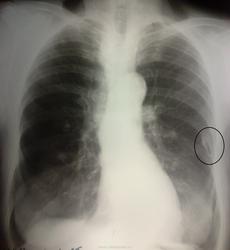

Плевральное наслоение слева+очаг справа на верхушке.

По всей видимости, тут будет, как ранее высказывался коллега, солидный "метатуберкулёзный архив" - там и петрификаты в бронхопульмональных с обеих сторон, и очаги справа (если не свежие, может, туберкуломы) - не менее трёх...

Добавил бы еще рекомендацию по УЗИ щитовидной железы, но изначальная "загагулина" совсем обидится. Описал бы последнюю как тень обызвествления в плащевой зоне на пятом ребре слева, в заключении - рекомендована левая боковая проекция.

Плевральная "козявка", в чем можно было бы убедиться, имея стандартный боковой.